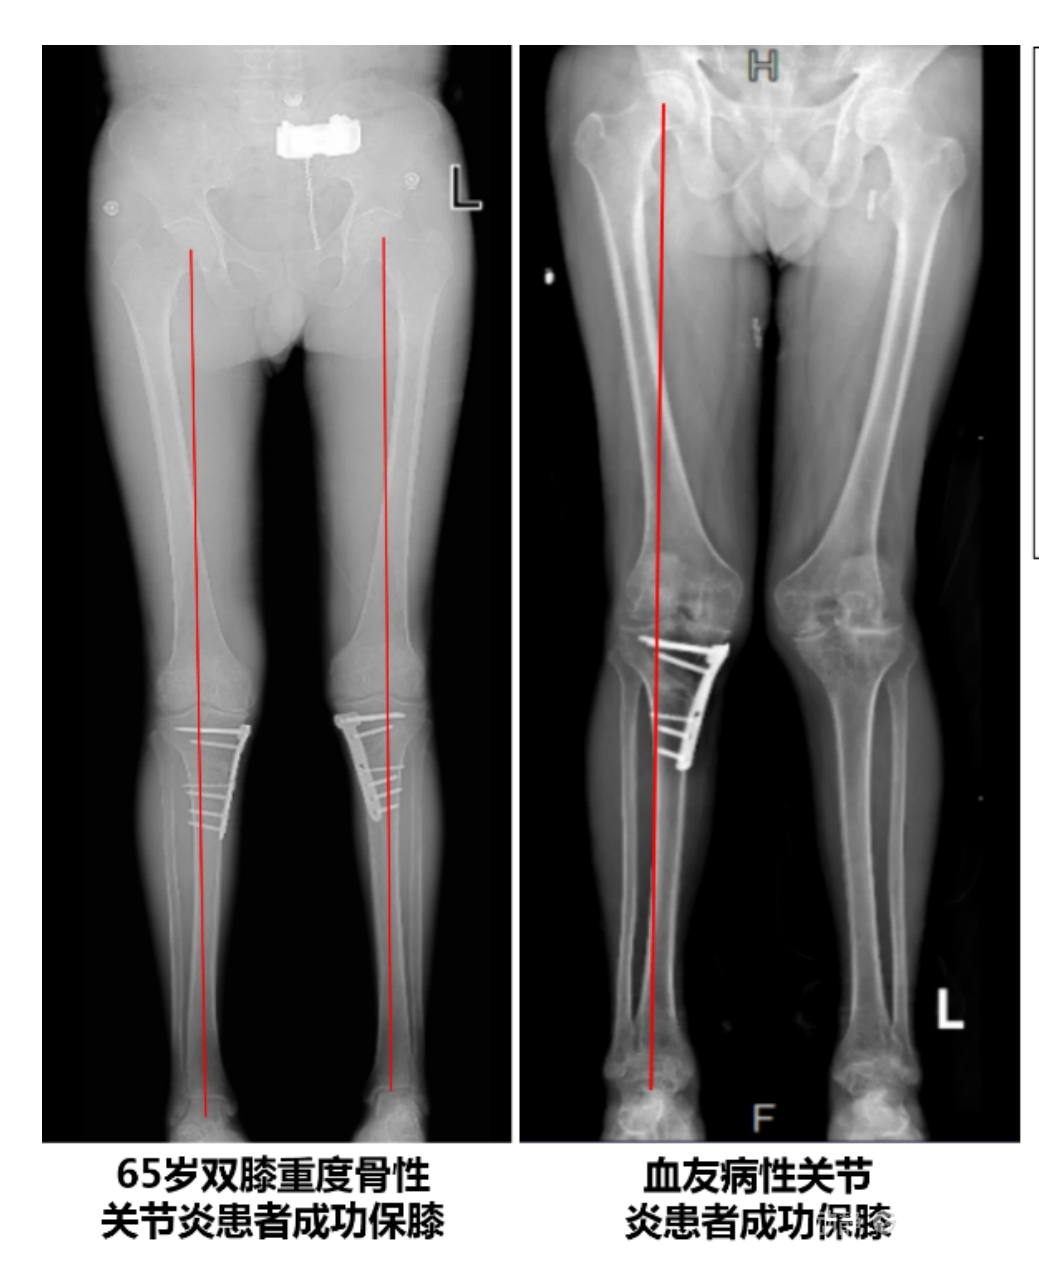

目前,APTT-HTO技術(shù)已成功應用于千余名患者,幫助保留自身膝關(guān)節。此類(lèi)保膝手術(shù)適用于單間室膝關(guān)節炎患者(如 “羅圈腿”),核心是通過(guò)調整力線(xiàn)糾正畸形,減輕磨損間室壓力、發(fā)揮健康間室作用,延長(cháng)膝關(guān)節壽命。若出現膝關(guān)節疼痛、保守治療無(wú)效且X線(xiàn)顯示關(guān)節間隙部分狹窄,建議及時(shí)就醫評估是否適合手術(shù)。

APTT-HTO脛骨高位截骨術(shù)